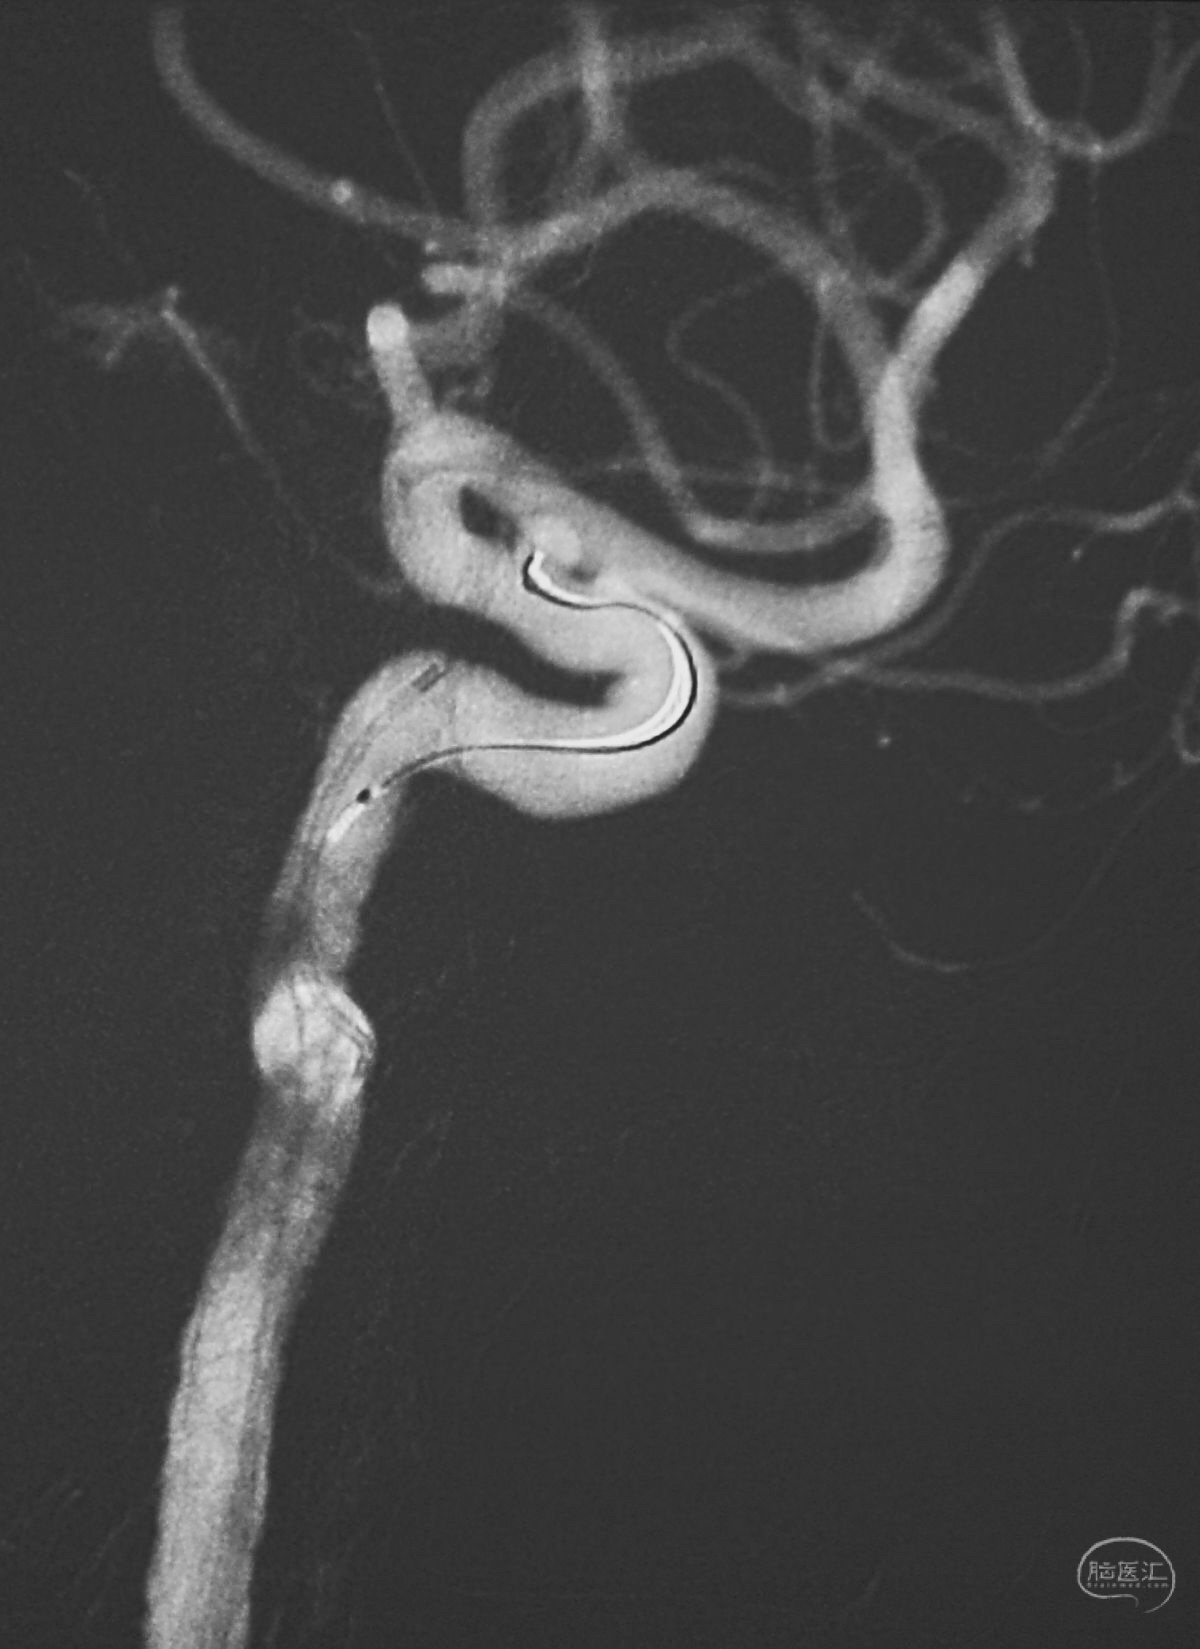

结束栓塞后不要直接撤管,要先把微导管往远心端送,使管头脱离瘤腔,再缓慢回撤。

微导管撤出后,完全释放Solitaire支架,可见突入载瘤动脉的弹簧圈被压回瘤腔。

术后左颈内动脉工作位造影和蒙片。